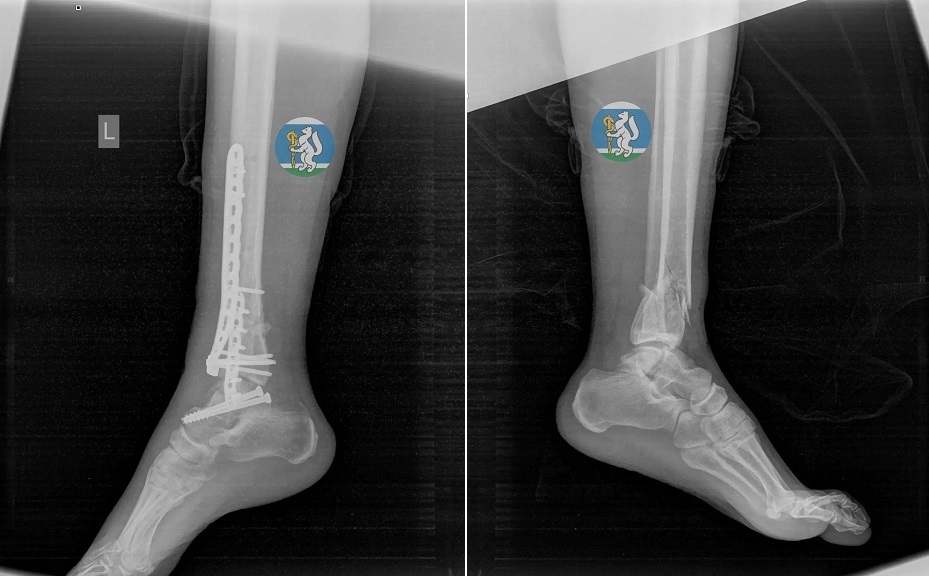

Об этой удивительной истории рассказали в свердловском минздраве. Бригада скорой помощи доставила женщину в состоянии травматического шока в профильную больницу. У пациентки диагностировали черепно-мозговую травму, повреждение шейного отдела позвоночника, множественные переломы костей таза, травму грудной клетки с повреждением легких, открытые оскольчатые переломы левой ноги. Первой задачей врачебной бригады было вывести пострадавшую из шокового состояния, зафиксировать переломы, остановить кровотечение. Несколько часов молодая женщина провела в операционной на грани жизни и смерти.

После экстренной операции екатеринбурженка находилась в реанимации на искусственной вентиляции легких до полной стабилизации состояния. Через полторы недели ее перевели в отделение травматологии, а еще через две недели врачи успешно выполнили операцию по частичному демонтажу аппаратов внешней фиксации и синтезу сломанных костей.

Лечение последствий тяжелейшей травмы шло поэтапно. Благодаря выбранной врачебной тактике ранней активации и вертикализации молодая женщина снова начала двигаться. В общей сложности в больнице пациентка провела месяц, после чего ее выписали. Сейчас она проходит курс реабилитации по ОМС.